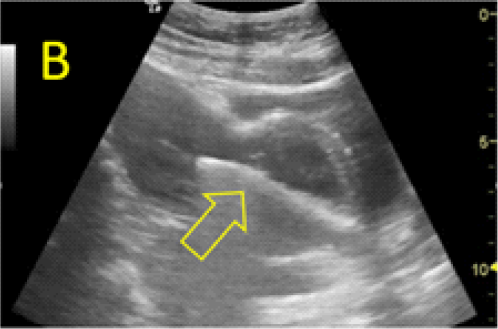

Figure 3 – Ultrasound evaluations on Day 3 (A, B) and 7 (C, D) after MTX administration, with B-hCG values of 103.016 and 57.710mUI/ml, respectively. Fetal growth and normal heart activity is present.

assessment revealed the persistence of embryonic cardiac activity and intense trophoblastic vascularization. HCG constantly decreased to 57,710mUI/ml on day 7 after MTX administration but the embryonic cardiac activity was still noted with a normal rate.